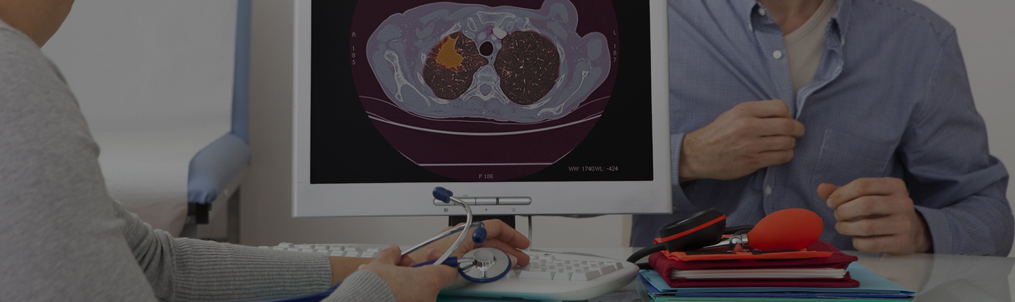

A CT scan can reveal small lesions in your lungs that might not be detected on an X-ray. A CT scan can

also provide precise information about the size, shape, and position of any lung tumours and can help

find enlarged lymph nodes that might contain cancer that has spread from the lung. To know more Click Here